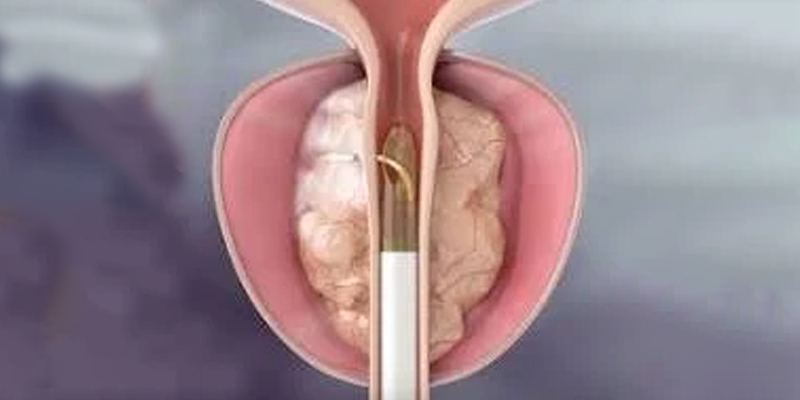

Benign Prostate Enlargement (BPH)

Minimally Invasive Prostate Procedures

Mr Michael Wanis is a consultant Urological Surgeon and Andrologist who provides assessment and treatment for Benign prostate enlargement, Erectile dysfunction, Haematuria (blood in the urine), Kidney stones, Shockwave therapy, Foreskin problems, Scrotal swelling and Aquablation. During your consultation, you will be informed of the most suitable options following a personalised evaluation.